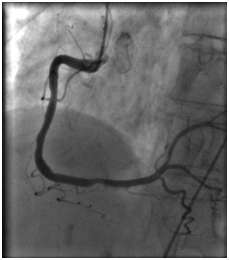

18.08.2011 выполнена селективная коронарная ангиография.

В процессе процедуры выявлено: ствол левой коронарной артерии обычно расположен. Передняя нисходящая артерия – в средней трети стеноз 80%.

Огибающая коронарная артерия без признаков стенозирующего атеросклероза.

Правая коронарная артерия – в средней трети стеноз 70%. Правый тип коронарного кровообращения.

Правая коронарная артерия